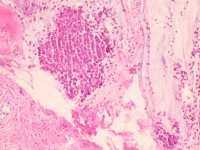

宫颈活检组织

性别

女

年龄

43岁

临床诊断

宫颈病变

一般病史

宫颈癌筛查:hpv16(+))

标本名称

宫颈组织

大体所见

灰白色组织

老师们看看,高级别累腺吗